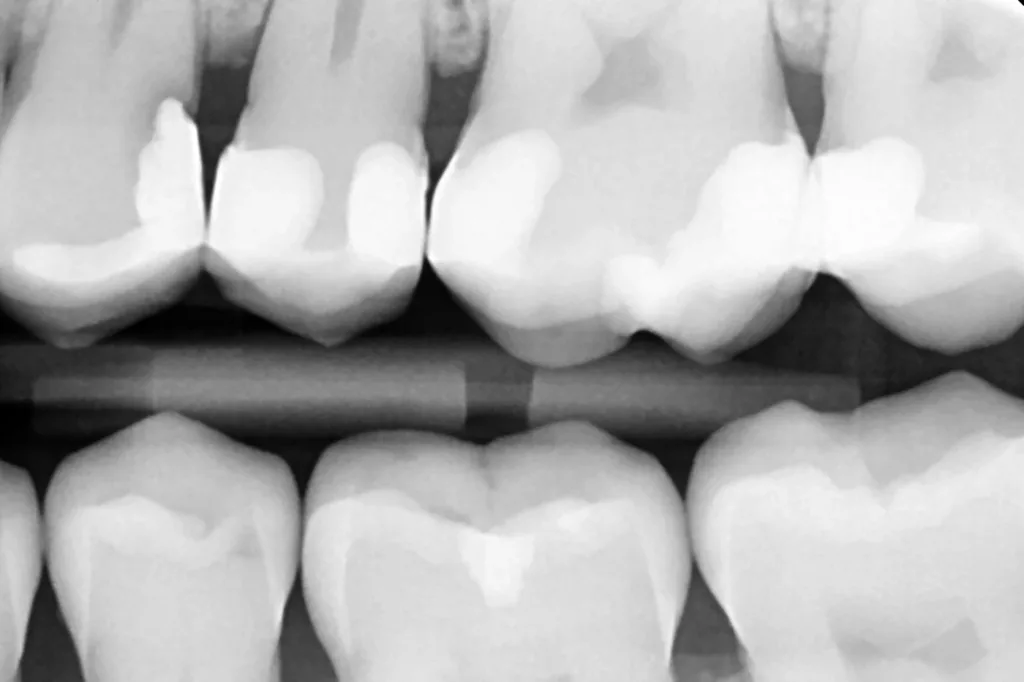

Die Abbildung 10 zeigt das Behandlungsergebnis unmittelbar nach Ausarbeitung und Politur (Diacomp Plus Twist, EVE), die Abbildung 11 bei einer weiteren Kontrolle nach sechs Monaten. In diesem Kontrolltermin wurden dann im routinemäßigen, zwei- bis dreijährigen Intervall Bissflügelröntgenaufnahmen zur Kariesdiagnostik angefertigt. Auf der Röntgenaufnahme zeigt sich die neue Visalys-Bulk-Flow-Restauration als randdicht, anatomisch korrekt geformt und ausreichend röntgenopak (Abb. 12). Die Schmelzläsion mesial an den Zähnen 15 und 16 erschien nicht therapiebedürftig, da die Oberfläche intakt war, wohl aber die versteckte Dentinläsion distal an dem Zahn 15. Der Defekt wurde in einem weiteren Termin identisch mit denselben Materialkombinationen und identischem Polymerisationsprotokoll versorgt (Abb. 13 bis 15).

Das Auffüllen des Slot-Defektes erfolgte in einem Zug erneut mit dem Einfarben-Bulkflow Visalys Bulk Flow (Abb. 30). Nach Polymerisation für 20 Sek. von okklusal (Elipar Deep Cure), Nachpolymerisation über die Randleiste und von bukkal für jeweils weitere 20 Sek. sowie der Ausarbeitung und Politur präsentierte sich erneut ein funktionell stabiles und ästhetisch ansprechendes Ergebnis (Abb. 31). Eine in der Sitzung durchgeführte routinemäßige Bissflügelaufnahme zeigt die randdichte Minifüllung und die gute Röntgenopazität (Abb. 32).

Diesmal war es eine defekte Approximalfüllung an Zahn 26, die ausgetauscht werden musste (Abb. 38). Der Patient erschien als Schmerz- und Neupatient. Nach Exkavation und Einschalung des Defektes analog zu den vorangestellten Fällen (Abb. 39) erfolgten die adhäsive Versiegelung und die restaurative Versorgung des Zahnes mit der identischen Materialkombination (G2 Universal, Visalys Bulk Flow). Die Abbildung 40 zeigt die ausgearbeitete und polierte adhäsive Restauration, die Abbildung 41 eine Bissflügelaufnahme in einem Folgetermin zu einer regulären Kontrolluntersuchung.

Hier fiel auch der approximal-zervikale Defekt distal an Zahn 24 auf, der in einem anschließenden Termin mit derselben Materialkombination versorgt wurde. Die Röntgenaufnahme verdeutlich den tief unterminierenden Defekt, der von dem Bulkflow-Material vollständig und blasenfrei aufgefüllt werden konnte.